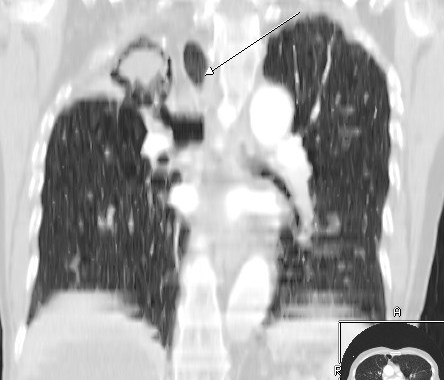

Air Mensicus Sign in Hydatid Disease

In chest roentgenograms, the pulmonary meniscus sign is a crescent-shaped inclusion of air surrounded by consolidated lung tissue. The common cause is aspergilloma. A hydatid cyst is, however, the most common cause in endemic areas. Cyst growth produces erosions in the bronchioles that are included in the pericyst, and, as a result, air is introduced between the pericyst and exocyst, producing the crescent or meniscus sign. Air penetrating the interior of the cyst may outline the inner surface of the exocyst, producing parallel arches of air that are referred to as Cumbo's sign with an “onion peel” appearance.